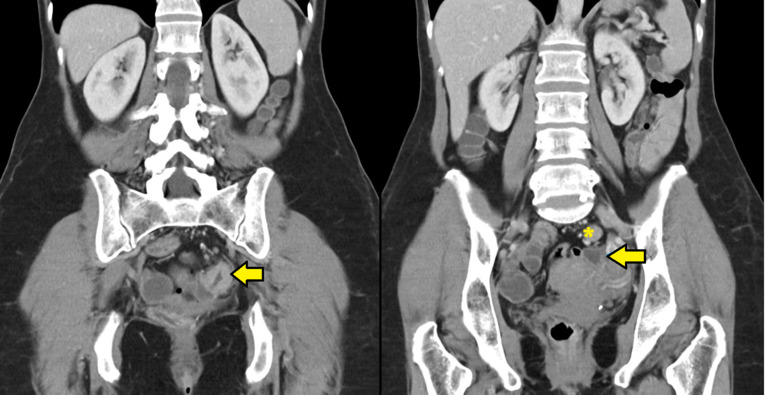

乳糜漏是手术损伤后病理性乳糜外渗进入腹腔。这是结直肠手术中一种罕见的并发症。在大多数情况下,保守治疗是有效的,尽管它往往需要延长住院时间。我们提出的情况下,60岁的女性乳糜漏后腹腔镜左结肠切除术和完整的肠系膜切除谁接受成功的门诊保守管理。我们在查阅的文献中没有发现其他保守门诊治疗成功的病例。充分的门诊管理可以通过降低医院费用和提高患者的生活质量提供显著的益处,同时在有指征时保持开始辅助治疗的可能性。

Chyle leak is a pathological extravasation of chyle into the peritoneal cavity after a surgical injury. It is an uncommon complication in colorectal surgery. In most cases, conservative treatment is effective, although it often entails prolonged hospital stays. We present the case of a 60-year-old female with chyle leak after laparoscopic left hemicolectomy with complete mesocolic excision who underwent successful outpatient conservative management. We found no other cases of successful conservative outpatient treatment in the consulted literature. Adequate outpatient management may provide significant benefits by reducing hospital costs and improving patient´s quality of life, while maintaining the possibility of starting adjuvant treatment if indicated.